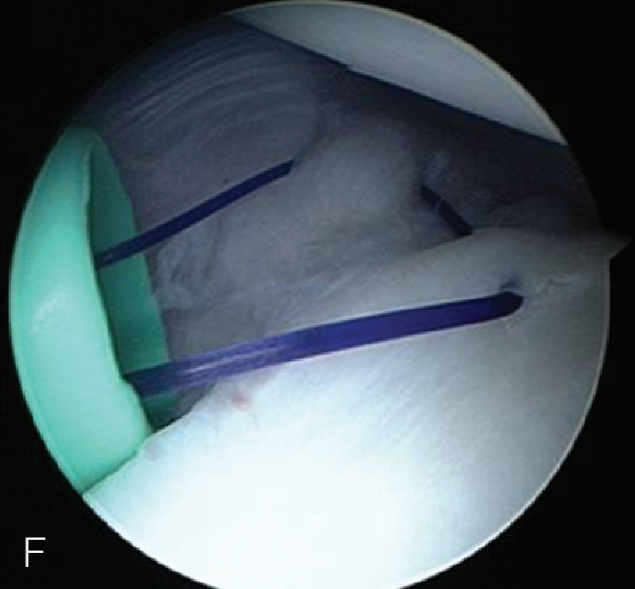

上盂唇修复

创建前方和后方入路时,与关节盂面成恰当角度,以便锚钉的置入。 高位和外侧放置前方入路可以有效地进行单纯上盂唇的修复。该入路位于肩袖间隙的高位和外侧,用腰椎穿刺针进行定位。非刚性套管有助于在肱二头肌腱附着部后方置入锚钉。 可用于 SLAP 修复的辅助入路包括 Wilmington 入路(肩峰后外侧角前方、外侧各 1 cm 处)或 Neviaser 入路(锁骨、肩峰、肩胛冈组成的三角形内,肩峰内侧 1 cm 处)。

B. 应首先用腰椎穿刺针确定辅助入路的恰当位置和方向。然后在皮肤上做一个小切 A B 口,钻头导向器置入关节。

修复处准备